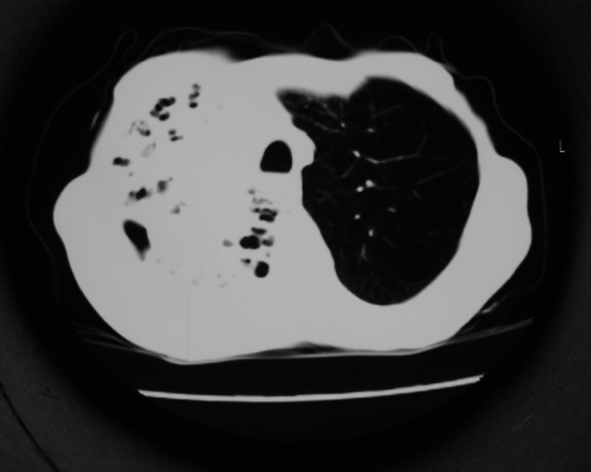

男53岁,咳嗽气短,以往身体健康.

1.右肺上叶干酪性肺炎,2。肺气肿,肺大泡

1.右肺上叶干酪性肺炎,2。肺气肿,肺大泡。支持!

支持右上肺继发性肺结核并干酪性肺炎,右肺大泡,左肺代偿性气肿。